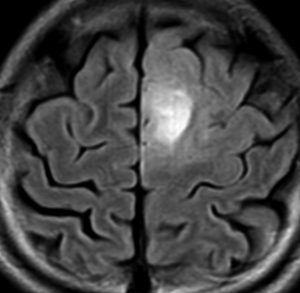

悪性転化 malignant transformation,膠芽腫への進展 progression

40代の患者さんです。夜間睡眠中の全般発作(症候性てんかん)で発症しました。フレア画像で左上前頭回に滲むような高信号領域(白い部分)がみられます。右側はガドリニウム増強MRIですが,全く増強されません。グレード2か3の星細胞腫あるいは乏突起膠腫を疑います。白く滲むような領域はよく見るとかなり広範囲に広がっています。

画像上では全摘出 gross total removalできて,病理診断は,退形成性乏突起星細胞腫 anaplastic oligoastrocytomaでした。IDH変異あり,1p/19q欠失なしです。現在の診断なら,退形成性星細胞腫 グレード3です。

手術後に54グレイの広範囲な局所放射線治療とテモゾロマイド化学療法を行いました。左の画像は放射線治療計画の時の線量分布図です。

5年後にいきなり激しい再発を生じました。再発部位は,放射線照射野外 out-of-fieldの前頭部帯状回でした。手術前に急速に増大して,画像所見も初回と全く違いました。摘出後の病理は,IDH1/2 wild type, 1p/19q intact, ATRX negative, MGMT met negative, MIB-1 40%という典型的な膠芽腫の所見でした。

この例とは異なって,退形成性星細胞腫の再発時には,IDH mutantのままの方が多いです。もしかすると先行した放射線誘発膠芽腫かもしれません。